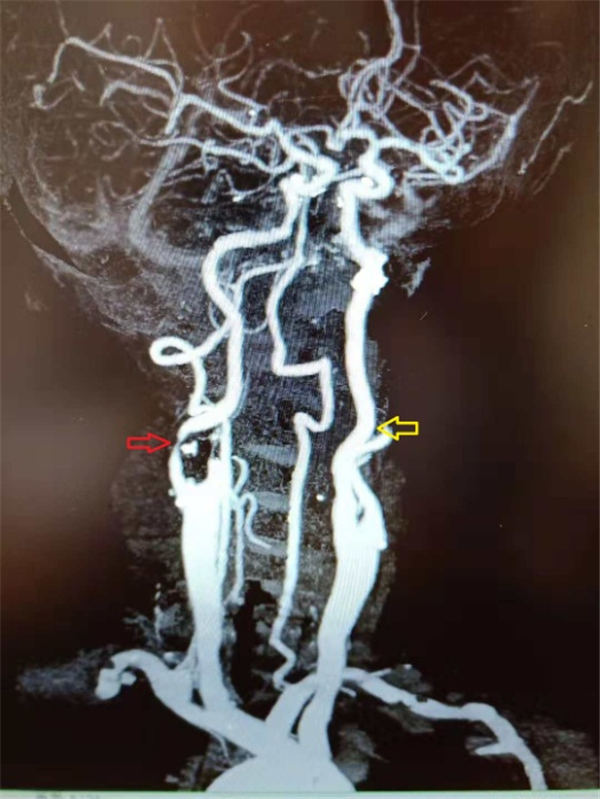

当天,老杜就顺利入住北京燕化医院,第三天就安排了介入手术:在右侧腹股沟局麻之后,穿刺股动脉插管到主动脉,再选择到右侧颈动脉造影,可见右侧颈内动脉重度狭窄、几近闭塞(上图红色箭头)。